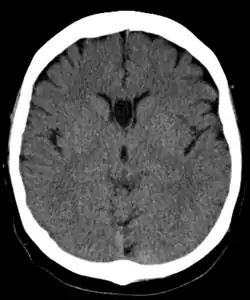

Cave of septum pellucidum seen on CT

The cave of septum pellucidum (CSP), cavum septi pellucidi, or cavity of septum pellucidum is a slit-like space in the septum pellucidum that is present in fetuses but usually fuses during infancy. The septum pellucidum is a thin, laminated translucent vertical membrane in the midline of the brain separating the anterior horns of the right and left lateral ventricles. It lies posterior to the corpus callosum. Persistence of the cave of septum pellucidum after infancy has been loosely associated with neural maldevelopment and several mental disorders that correlate with decreased brain tissue.[1][2][3][4][5]